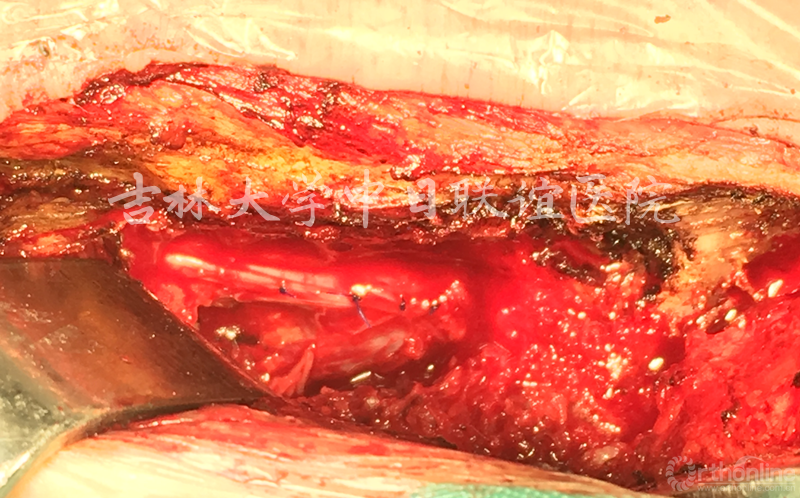

5.取出肿物后,在显微器械下精细缝合硬膜(如下图)。

术后病理:

神经鞘瘤(Neurinoma)